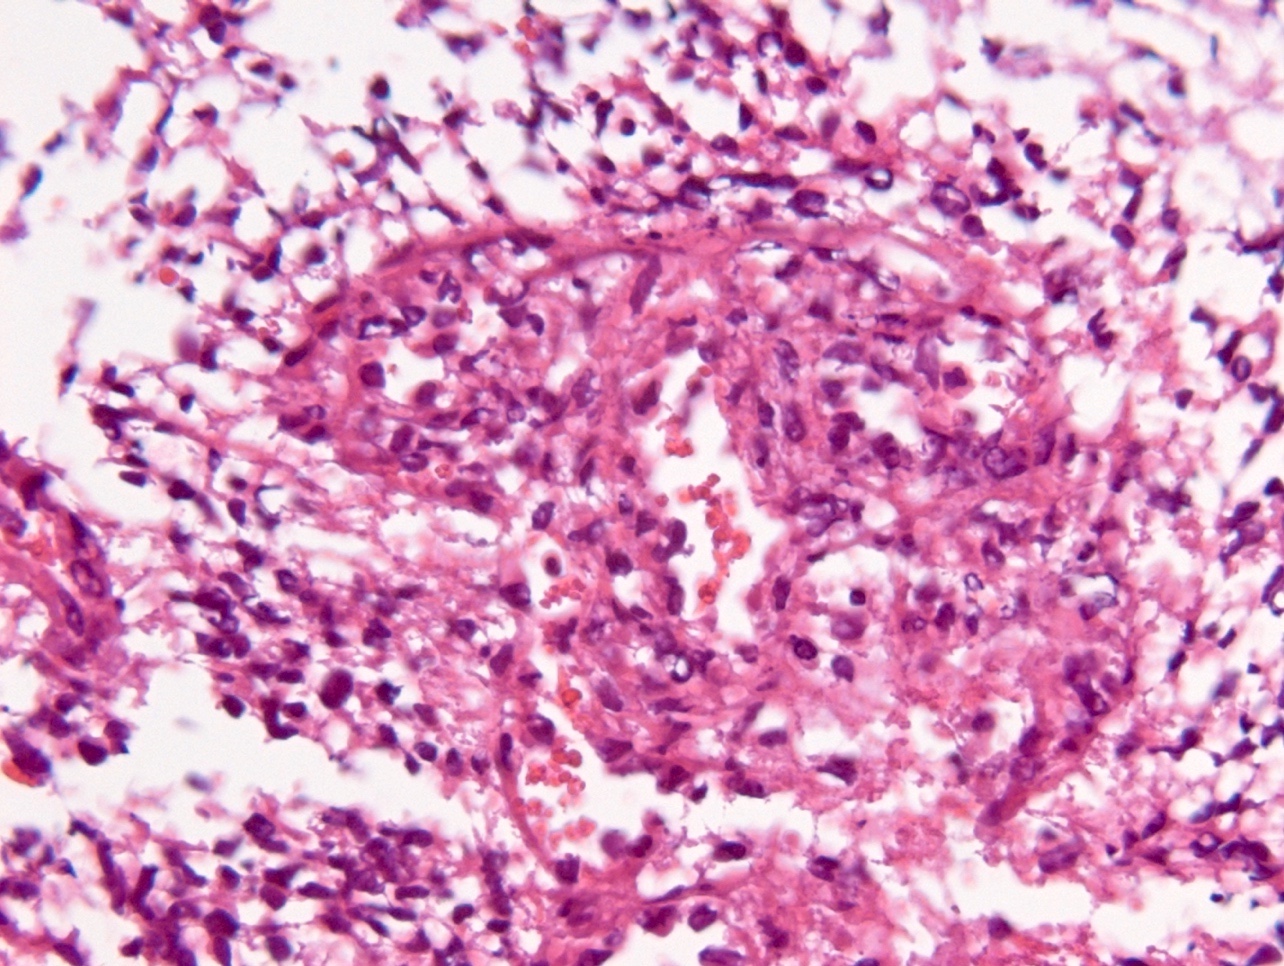

Microscopic (histologic) description

- Diffusely infiltrating tumor cells with oval to elongated astrocytic nuclei and varying appearance of tumor cytoplasm and fibrillar glial processes (Acta Neuropathol 2015;129:789)

- At the periphery, tumor cells may infiltrate in a diffuse single cell pattern, often with entrapped neurons and axons

- Cellular morphology is variable, even within a single tumor

- Commonly there is a mix of cells with elongated nuclei and fine fibrillar processes, cells with eccentric nuclei and glassy eosinophilic cytoplasm (gemistocytes), larger pleomorphic cells and small cells with scant cytoplasm

- May show oligodendroglioma-like areas

- Myxoid background and microcyst formation may be present

- Variable mitotic activity, cellularity and nuclear atypia depending on CNS WHO grade

- In small biopsy specimens, the presence of 1 mitosis may be sufficient for a CNS WHO grade 3 diagnosis, while the presence of a few mitotic figures in a large resection would not be sufficient for grade 3 designation (Acta Neuropathol 2020;139:603)

- Presence of necrosis or microvascular proliferation would be consistent with a CNS WHO grade 4 designation

Microscopic (histologic) images

Contributed by Eman Abdelzaher, M.D., Ph.D., John DeWitt, M.D., Ph.D. and Meaghan Morris, M.D., Ph.D.